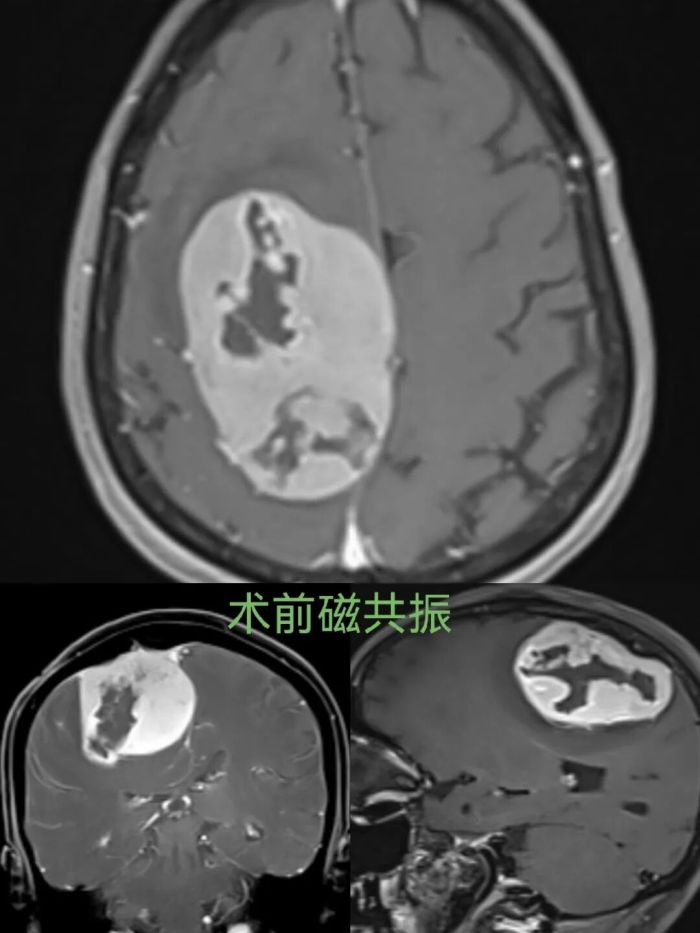

术前磁共振清晰显示,右侧额顶部巨大脑膜瘤对脑组织形成明显压迫。

65岁的蒋女士(化名),因颅内占位病变4年余,突发左侧肢体乏力1天紧急入住桂林医科大学第二附属医院。入院时她神志清楚,但左侧肢体偏瘫,右侧肌力正常,生活行动受到严重限制。头颅磁共振检查提示:右侧额顶部巨大脑膜瘤,肿瘤体积大、占位效应明显,正是导致肢体偏瘫的“元凶”。